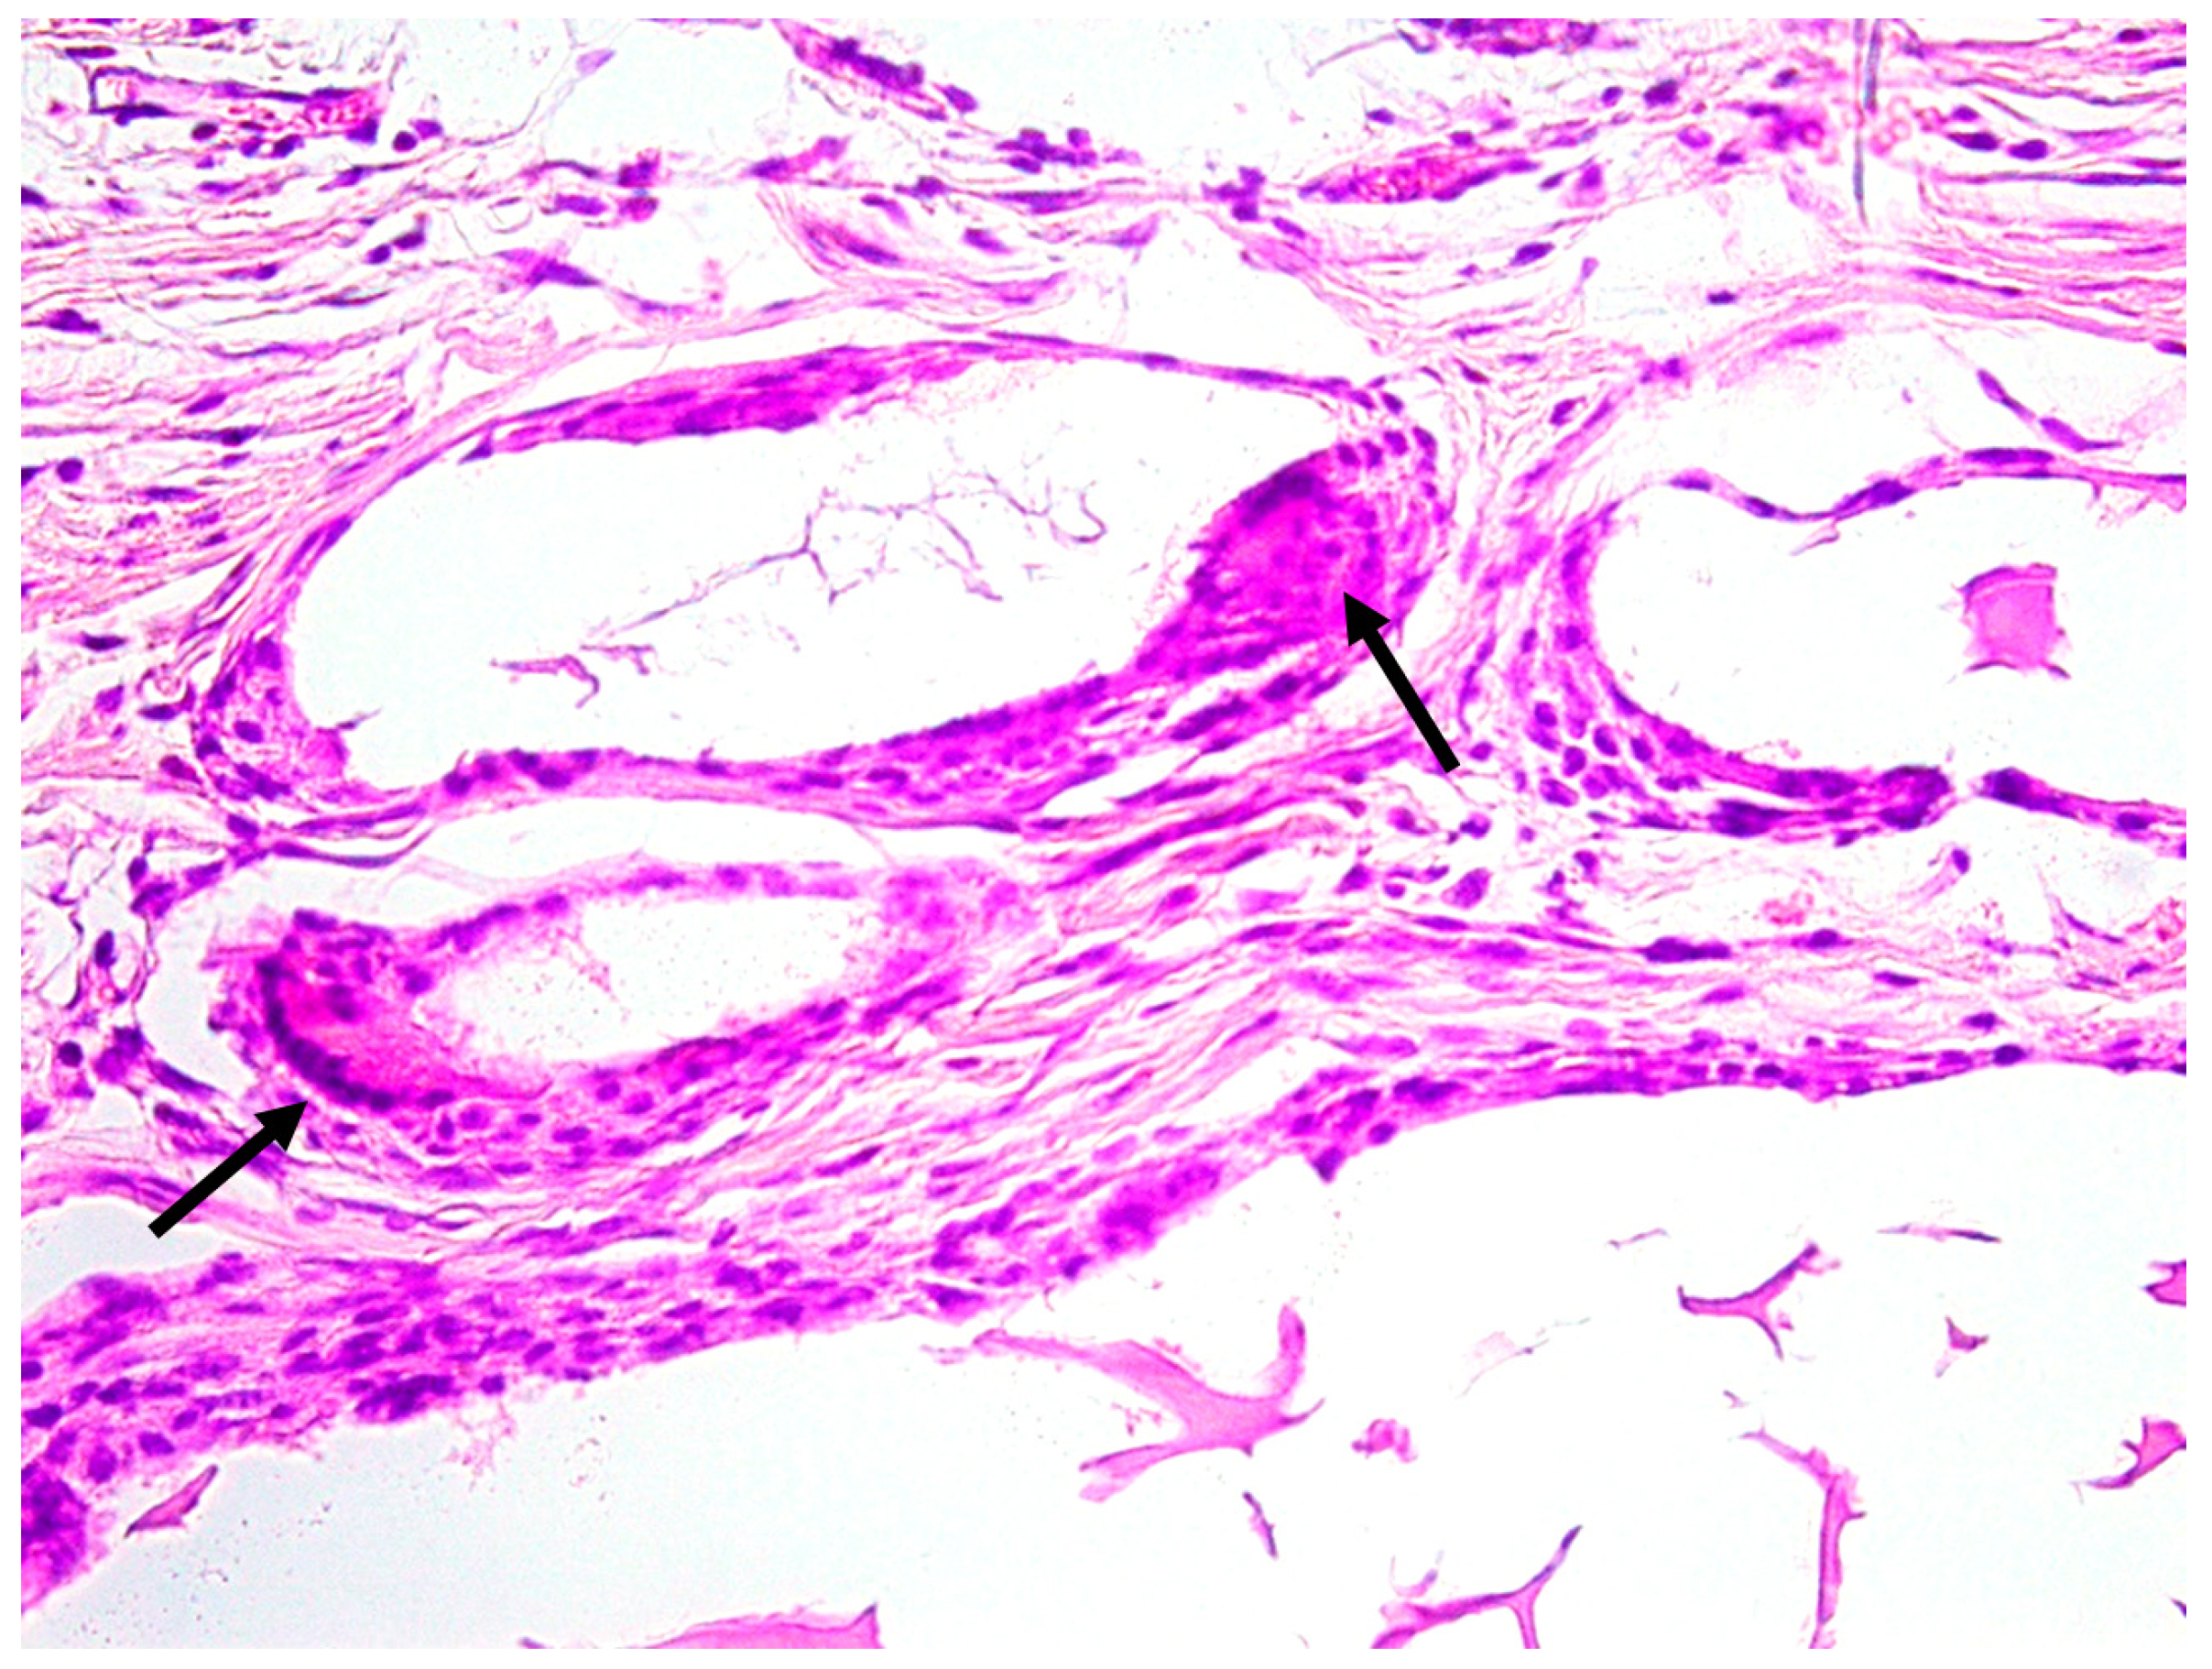

3.1. Qualitative Histological Analysis